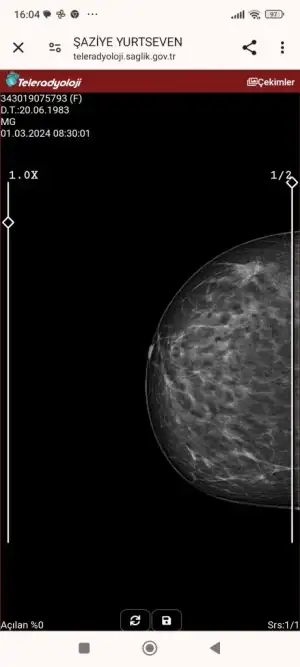

Merhaba arkadaşlar ben ara kanama sıklığı ve uzunluğu için doktora gittiğimde ve ablam rahim kanseri ameliyatında olduğu için aynı gün içinde hem rahim biyopsisi ve memografi çekildim memografi sonucu daha çıkmadı ama patoloji çıktı ikisine bir bakacağı için daha doktora gitmedim anlayan varmı acaba bakabilirmisiniz